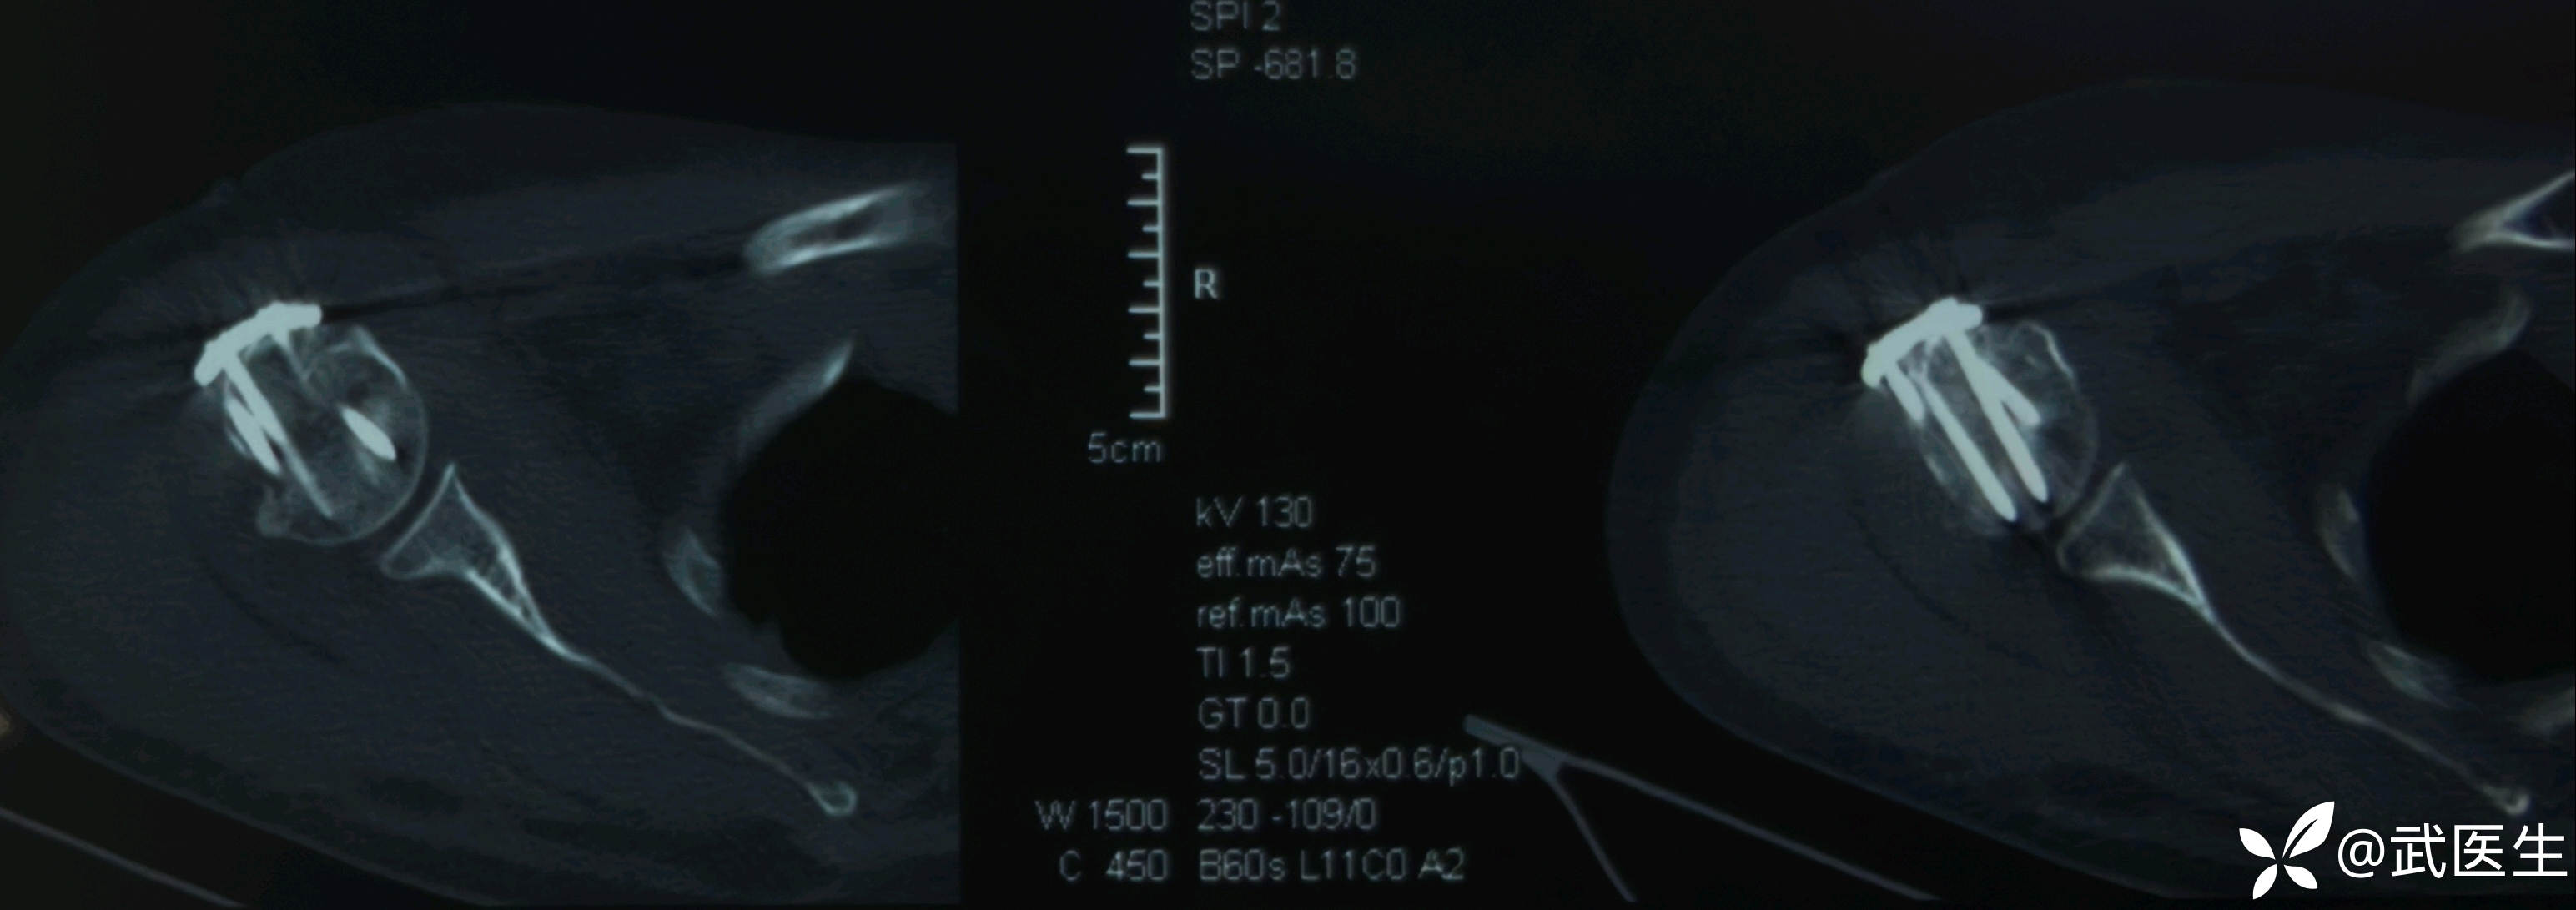

【治疗经过及结果】:入院完善检查,择期安排手术。患者年轻,肱骨外科颈骨折选择保头治疗。择期安排。

术中透视复位良好,术后CT验证一下